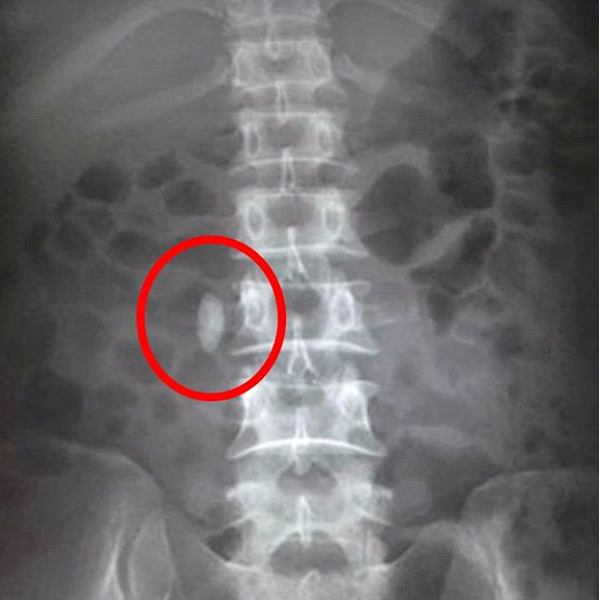

- X-quang hệ tiết niệu (KUB): có thể phát hiện sỏi niệu quản trong khoảng 60-80% trường hợp, ngoại trừ các loại sỏi không cản quang như sỏi axit uric, cysteine.